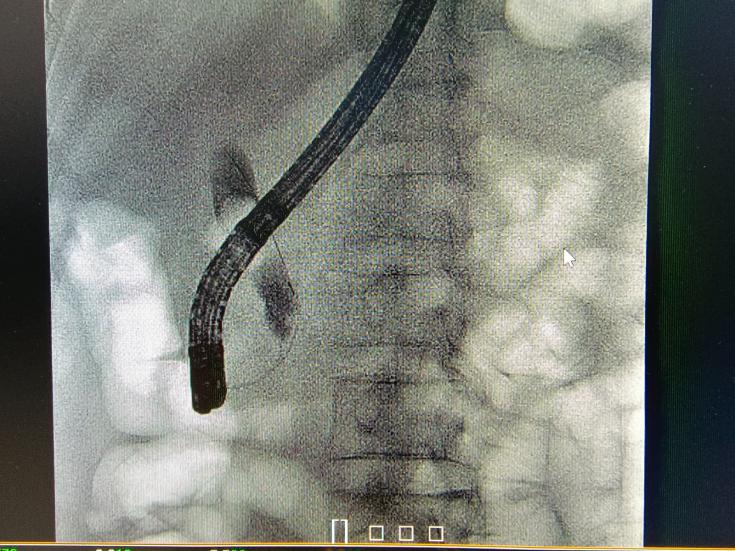

ERCP即经内镜逆行性胰胆管造影术(Endoscopic Retrograde Cholangio Pancreatography,ERCP)。通常是用十二指肠镜从口腔依次通过食道、胃,到达十二指肠乳头,并从十二指肠乳头开口处插入特制的导丝跟工具,通过导管向其内注入造影剂,在X光透视下观察胰管、胆管、胆囊显影并拍片。

简单来说,就是十二指肠镜经口进入,在十二指肠的乳头部进入胰胆管,在放射线造影导引下处理胰胆管病变,比如胆管结石,可以经口取出,不开刀,超级微创。